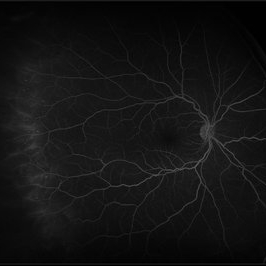

Central Retinal Artery Occlusion

Fluorescein angiogram of an 66-year-old female with a central retinal artery occlusion affecting her left eye.

Photographer: Olivia Rainey

Imaging device: Heidelberg Spectralis

Condition/keywords: 50 degrees, central retinal artery occlusion (CRAO), fluorescein angiogram (FA), left eye, mid phase, retinal ischemia